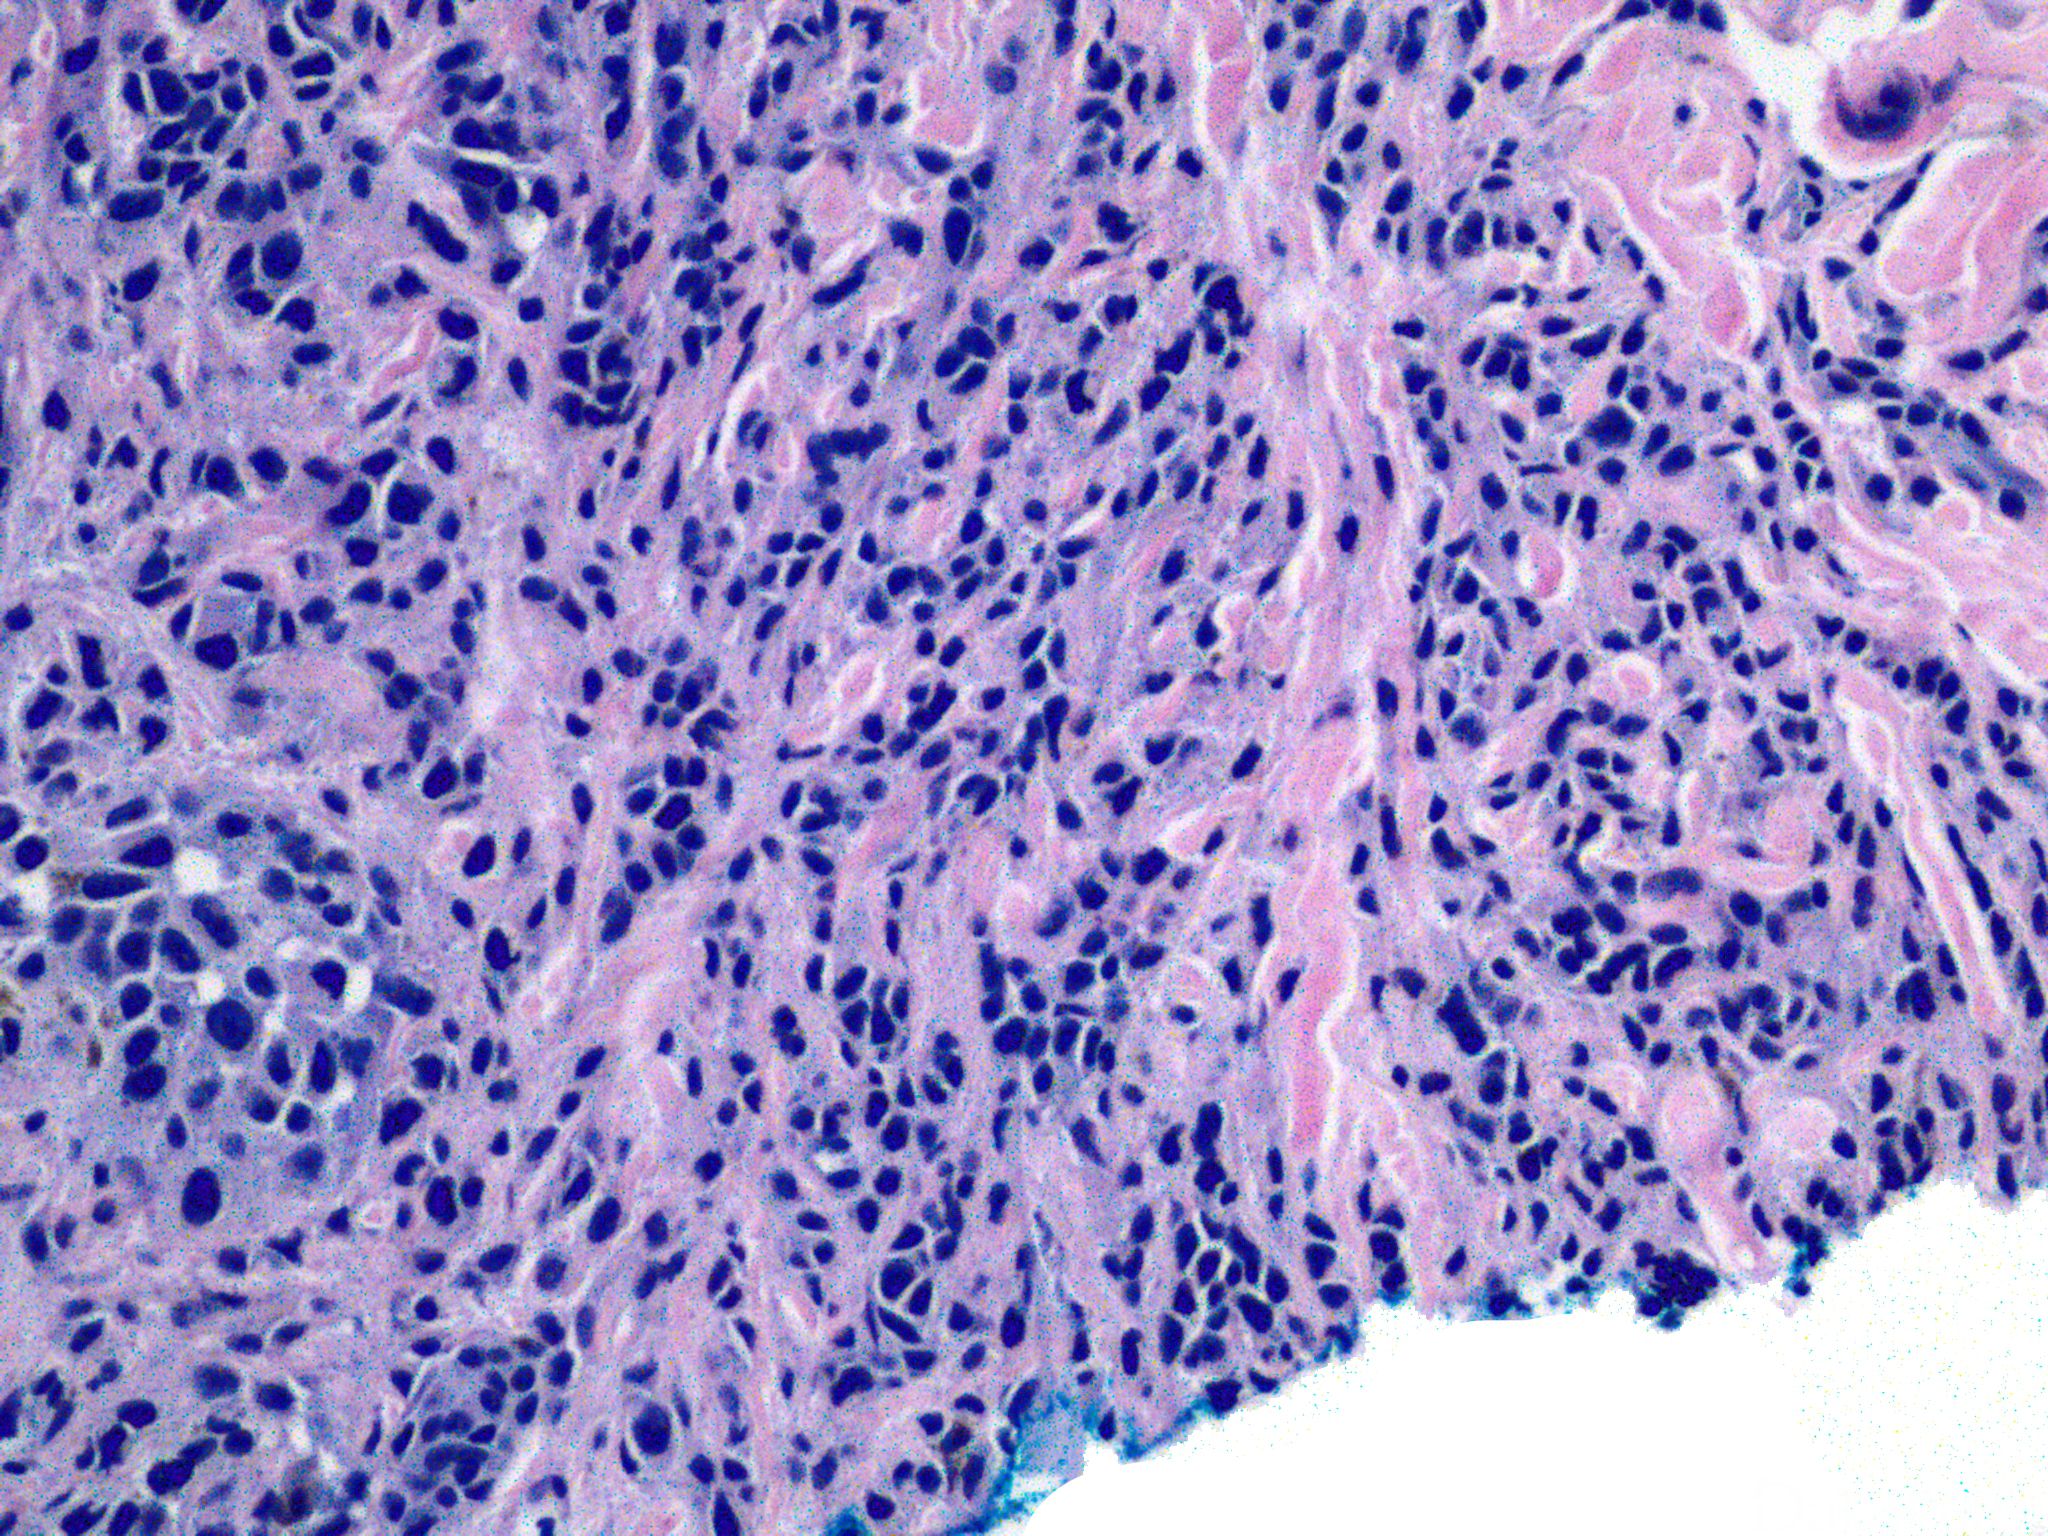

真皮内见肿瘤细胞呈黏附性结节状增生,具推进型边缘;

细胞通常为上皮样,也可能呈梭形或小细胞型,偶尔可见大细胞型;

表皮薄,可伴有溃疡;